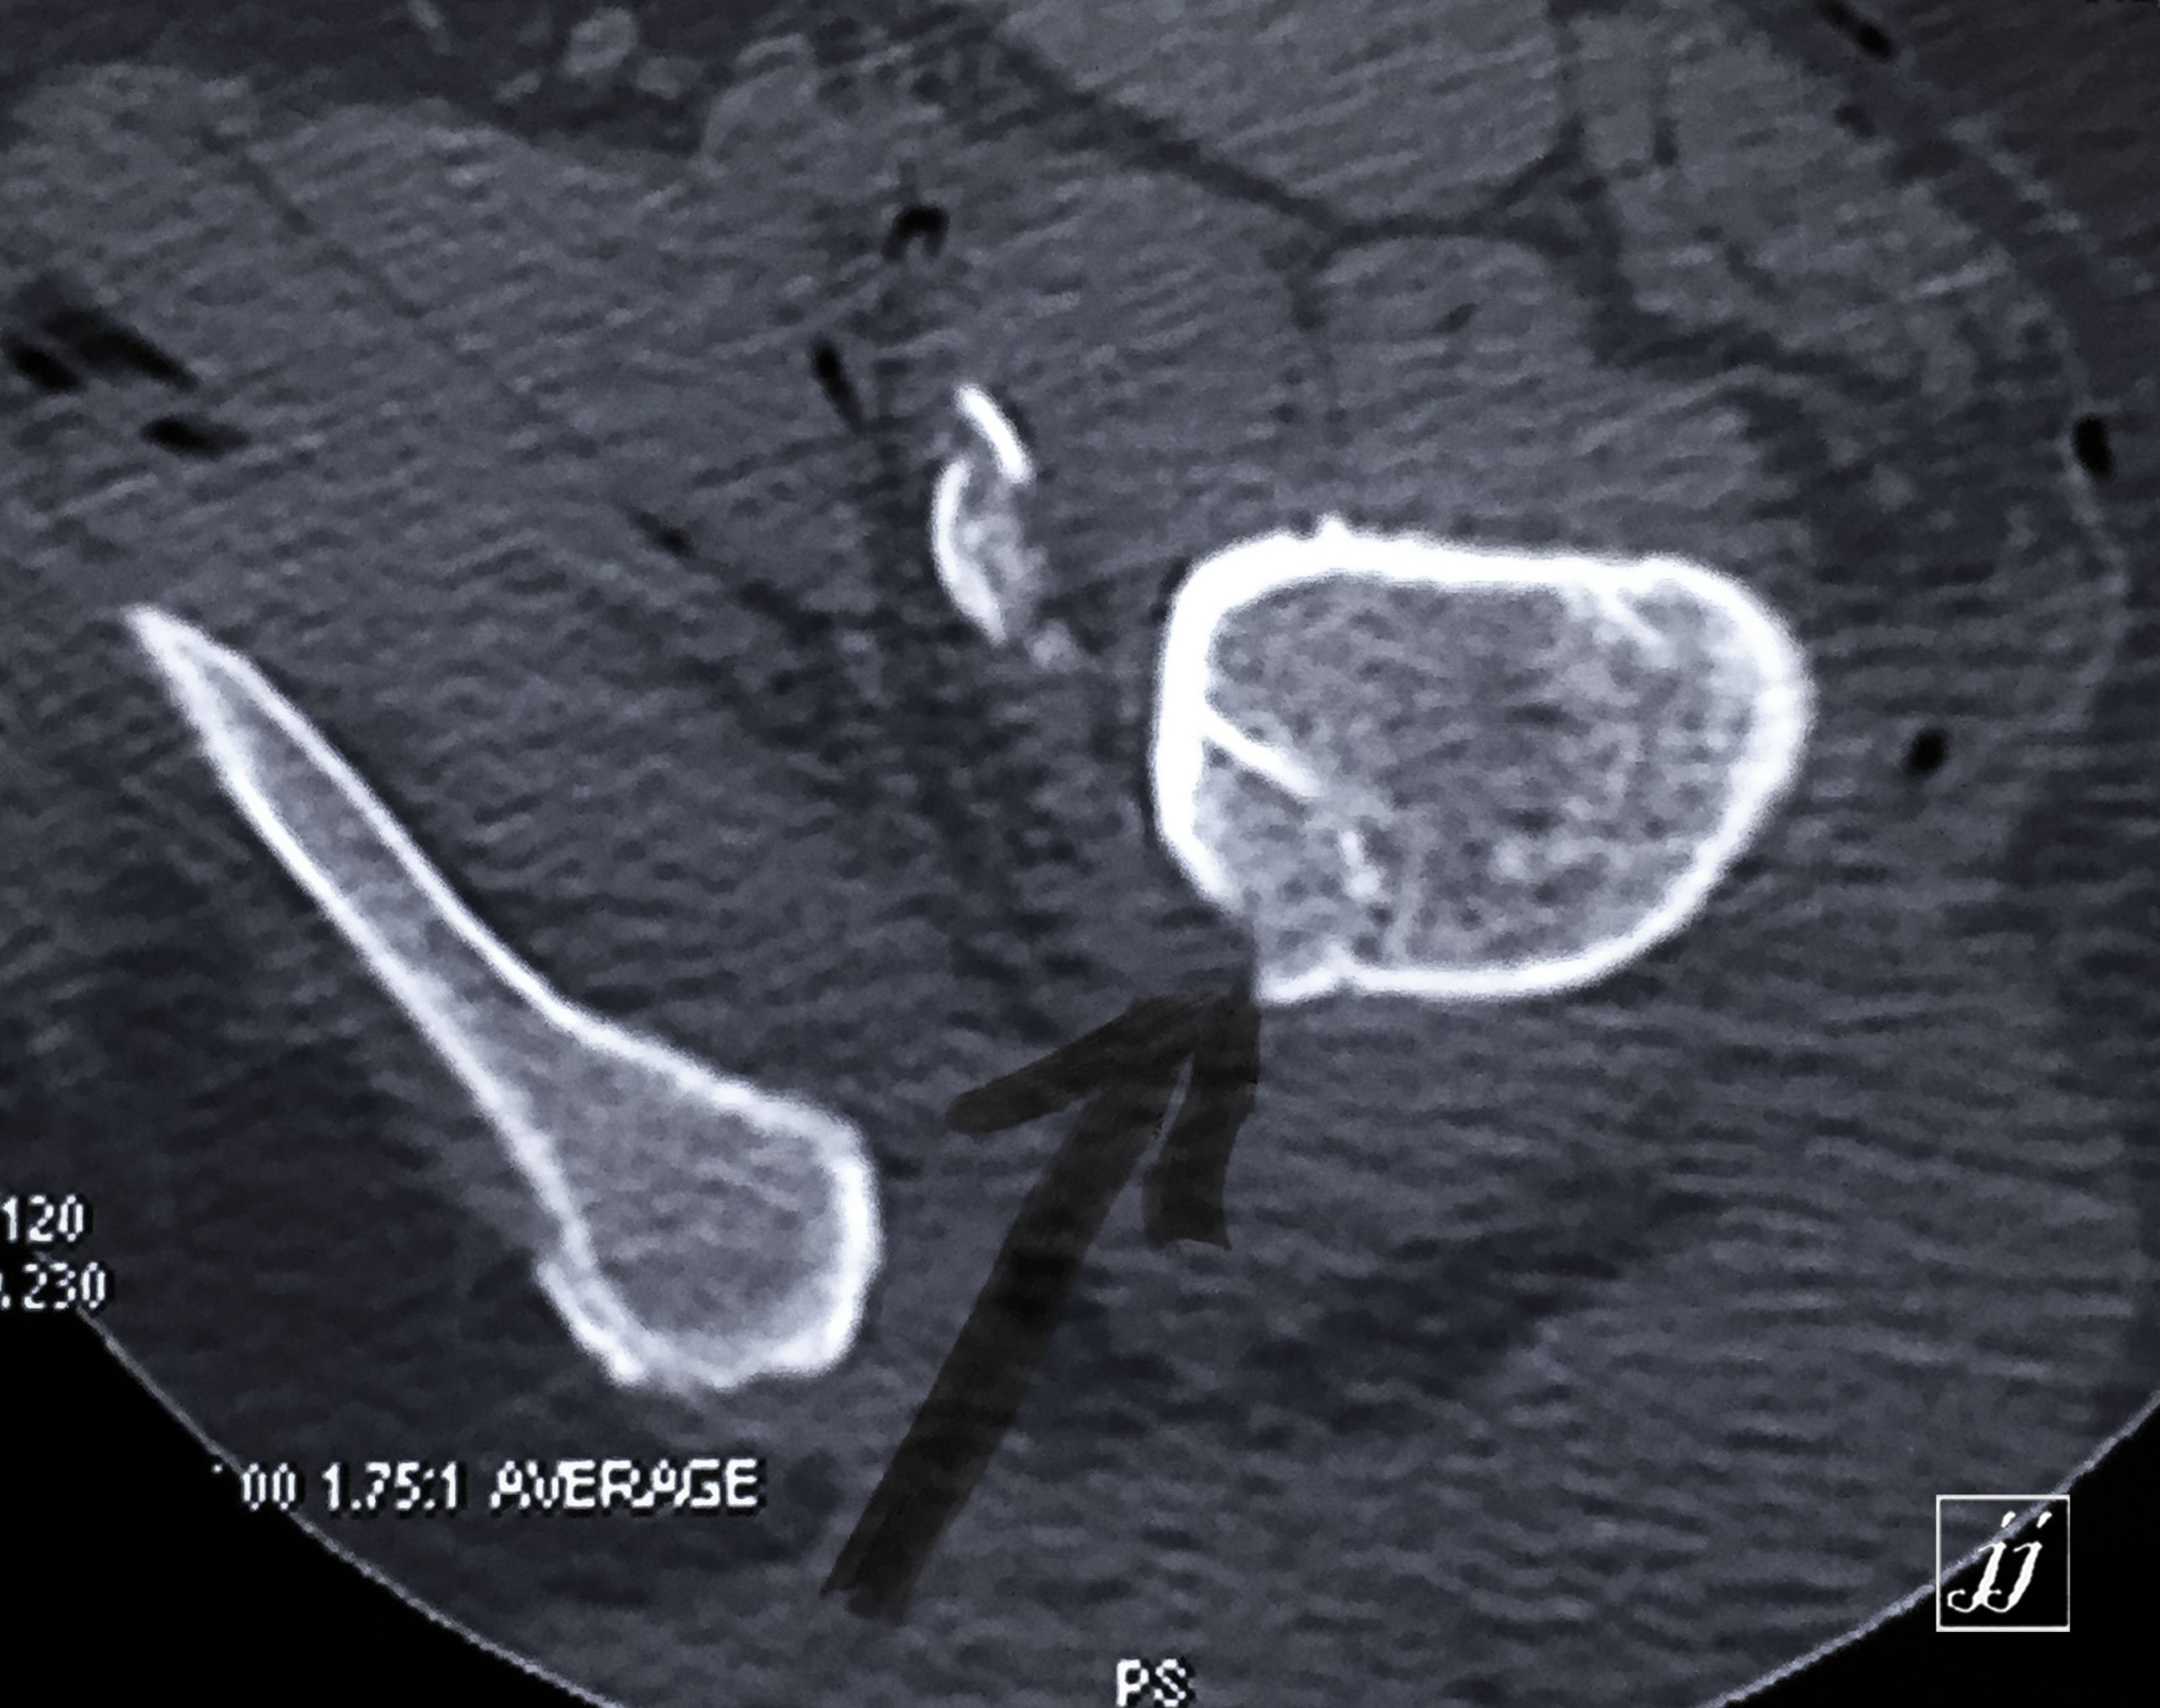

MSK- detached fracture of lesser trough chanter (10)